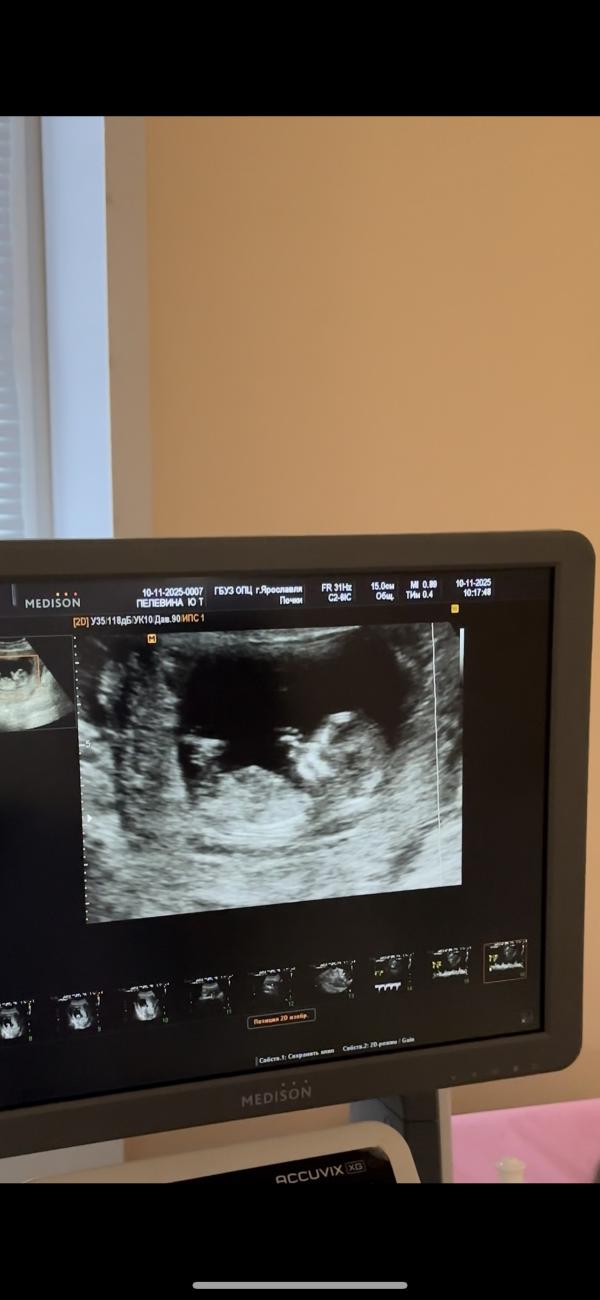

Прошли первый скрининг сегодня. Результат крови будет в следующий понедельник🤞🏼

По УЗИ все отлично, сказали. Малышка спала, на датчик не реагировала и не проснулась)

Мужу разрешили зайти под конец, записал видео)